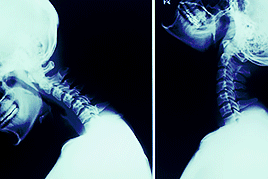

颈椎由椎骨、颈椎间盘、颈椎椎管、颈椎椎间孔、横突孔组成,虽然小,但承受的压力却很大。

当颈部活动时,两块椎骨会出现各种角度的开合,颈椎间盘就会配合椎骨来变换形状,日积月累,会造成劳损和压迫。

磨损会导致椎体间逐渐形成骨刺,韧带为了维持颈椎稳定而增生变厚。这时,椎管中的脊髓受到挤压和冲击,很容易受伤,从而引发脊髓型颈椎病。

同时,颈椎间盘、骨刺还可能压迫神经根,引发神经根型颈椎病。还可能损伤、压迫椎动脉和交感神经,造成椎动脉型颈椎病、交感神经型颈椎病。